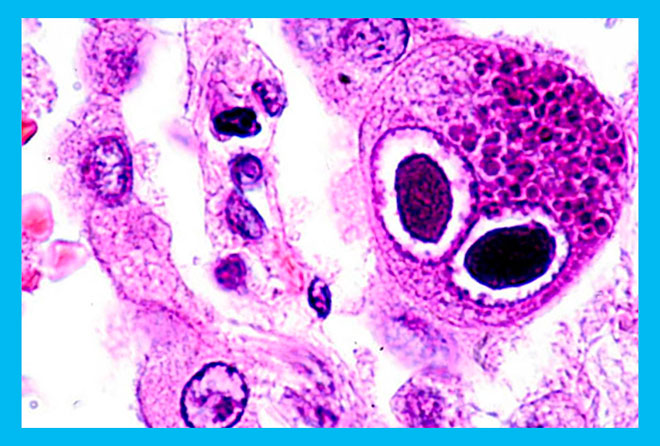

ЦМВ относится к семейству герпесвирусов и имеет соответствующую медицинскую классификацию – вирус герпеса человека 5-го типа. Самый распространенный путь заражения через слюну. Поэтому чаще всего вирус обнаруживают при исследовании секрета слюнных желез. Особенно неприятно услышать подобный результат при планировании беременности.

Существует несколько основных способов обнаружения цитомегаловируса перед беременностью: цитологический анализ, бактериологический посев, иммуноферментный анализ и полимеразная реакция. Цитологический и бактериологический анализы используют для фактического обнаружения вируса. Для выявления антител вырабатываемых иммунитетом используют ИФА (иммуноферментный анализ). Данные этого анализа позволяют определить степень опасности для плода.